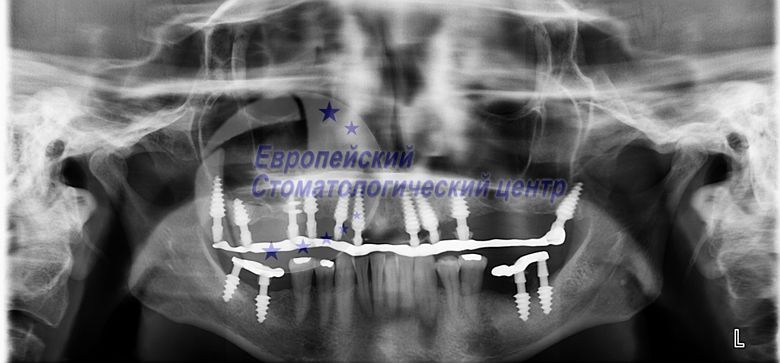

В данной клинической ситуации были жалобы на отсутствие зубов, на эстетический дефект. На ортопантомограмме (опг) видны периодонтитные зубы которые подлежат удалению. Так же видим недостаточный объем костной ткани на верхней челюсти. И невозможную установку имплантатов классическим способом без восстановления объема кости. Было принято решение удалить все инфицированные зубы на верхней челюсти с немедленной установкой одноэтапных и базальных имплантатов в одно посещение в лунки удаленных зубов. Лунки удаленных зубов обрабатывались эрбиевым лазером. Через день после операции установлены временные коронки. Через четыре месяца после операции временные коронки поменялись на постоянные из биологически инертного материал РЕЕК.

опг через день после операции